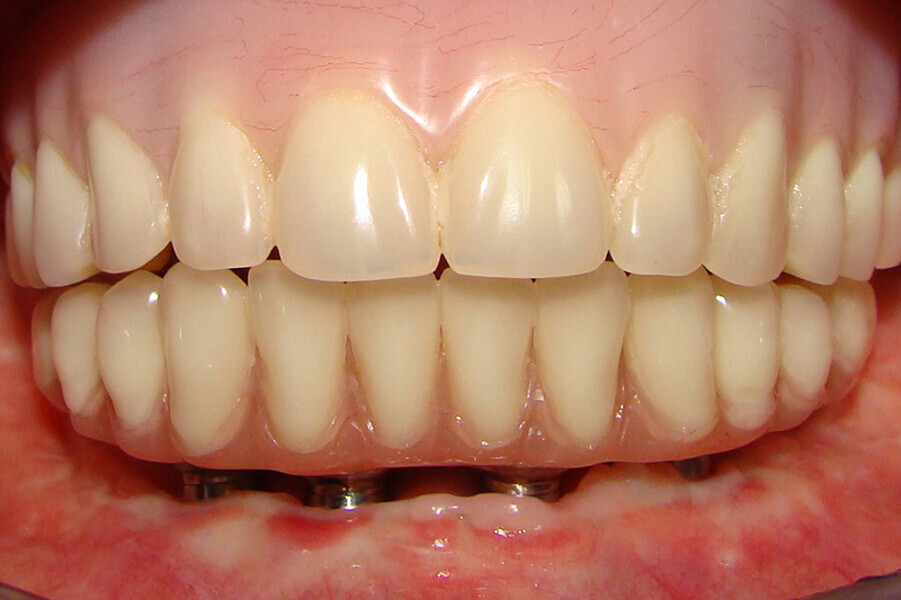

Fig. 6. Prótesis Híbrida inmediata y radiografía control con 6 años post-operatorio